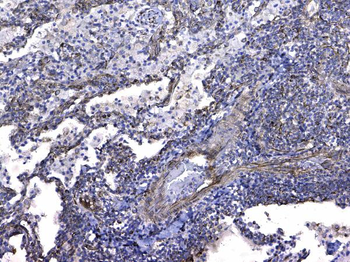

- Anti-GSTM3 Antibody [orb402287]

ELISA, IHC, WB

Human, Mouse, Rat

Rabbit

Polyclonal

Unconjugated

10 μg, 100 μg - Anti-S100 alpha 6/S100A6 Antibody [orb315184]